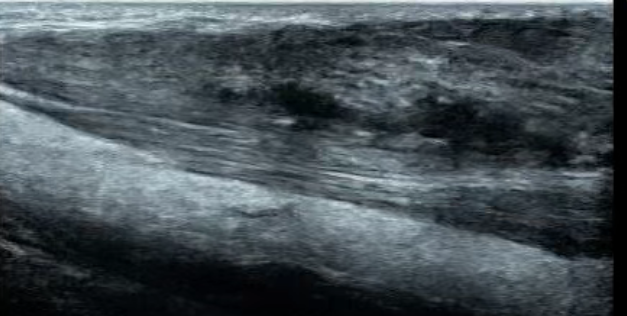

患者女,45岁。因现双侧跟腱肿物多年,2年前手术切除,病理诊断黄色瘤,目前术后复发来就诊。肉眼可见跟腱不均匀增粗,双侧髌腱、双手伸肌腱等多处结节状病变。超声表现:上述肌腱···...